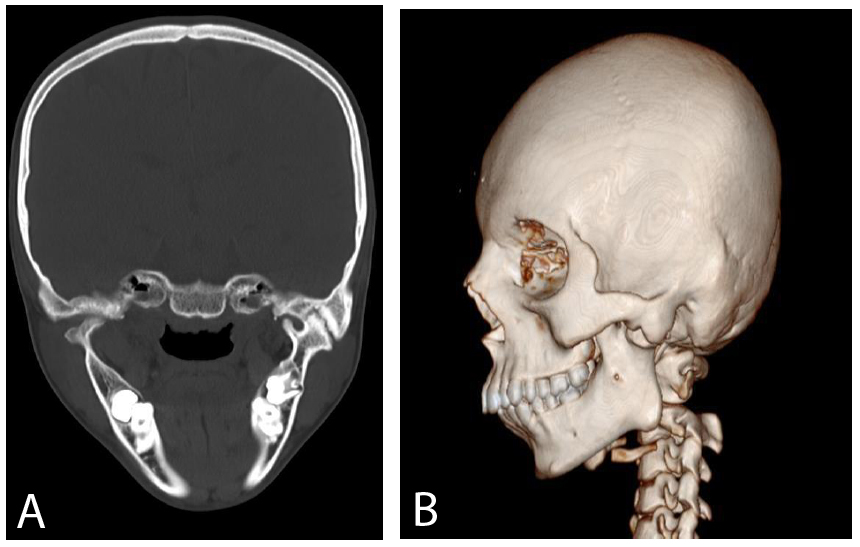

The provisional diagnosis for this was Traumatic TMJ Ankylosis of the left side. To confirm the same, CT Face was conducted with 3D reconstruction in all Coronal, axial, and sagittal sections of 1.5 mm slices. Reports were suggestive of Bony ankylosis of the TMJ of the left side (Fig. 2A-B).

CT scan (showing TM joint ankylosis over the left side).

A. Coronal VIEW B. 3DCT.